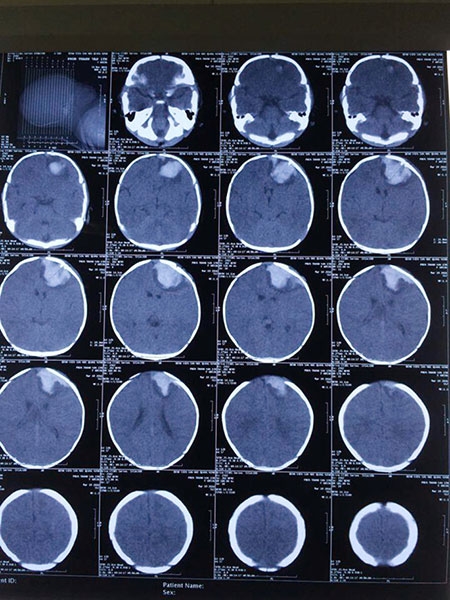

Trao đổi với Tuổi Trẻ, ông Nguyễn Quốc Hùng, Gíam đốc Bệnh viện sản nhi Quảng Ninh, phẫu thuật viên của ca mổ cho biết qua chụp cắt lớp gần 2 ngày sau phẫu thuật, bé Vân tạm ổn. Tuy nhiên khả năng phục hồi còn đợi thêm thời gian mới có thể đánh giá.

| Hình ảnh chụp CT |